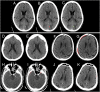

Computed tomography (CT) of the head is used worldwide to diagnose neurologic emergencies. However, expertise is required to interpret these scans, and even highly trained experts may miss subtle life-threatening findings. For head CT, a unique challenge is to identify, with perfect or near-perfect sensitivity and very high specificity, often small subtle abnormalities on a multislice cross-sectional (three-dimensional [3D]) imaging modality that is characterized by poor soft tissue contrast, low signal-to-noise using current low radiation-dose protocols, and a high incidence of artifacts. We trained a fully convolutional neural network with 4,396 head CT scans performed at the University of California at San Francisco and affiliated hospitals and compared the algorithm's performance to that of 4 American Board of Radiology (ABR) certified radiologists on an independent test set of 200 randomly selected head CT scans. Our algorithm demonstrated the highest accuracy to date for this clinical application, with a receiver operating characteristic (ROC) area under the curve (AUC) of 0.991 ± 0.006 for identification of examinations positive for acute intracranial hemorrhage, and also exceeded the performance of 2 of 4 radiologists. We demonstrate an end-to-end network that performs joint classification and segmentation with examination-level classification comparable to experts, in addition to robust localization of abnormalities, including some that are missed by radiologists, both of which are critically important elements for this application.